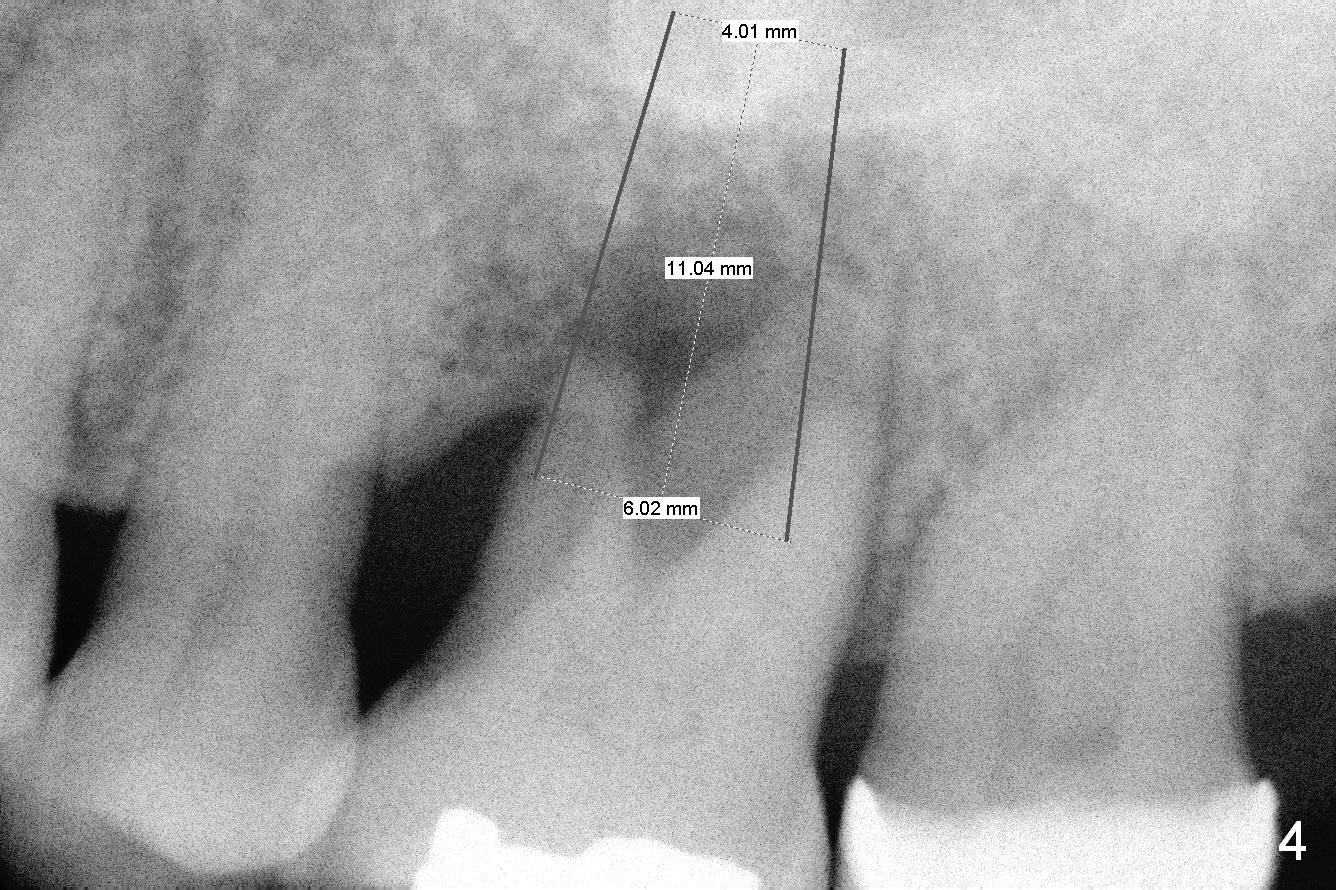

A 54-year-old woman has history of chronic periodontitis with bruxism. Bone loss at the tooth #14 starts at the mesial crest (Fig.1: 2008), extends to the mesial root (Fig.2, 2015) and the palatal one (Fig.3, 2016). The periodontal pockets are deep with mobility III. Since the defect is large with low bone density, Magic osteotomes are going to be used for CMC immediately after extraction (Clindamycin). If there is no history of sinusitis, a 11 mm long implant will be placed (Fig.4). Allograft (.5-1.5 mm) will be delivered with the large bone carrier for CMC (prior to implant placement) and the amalgam carriers for socket gap closure (before and after implant placement).